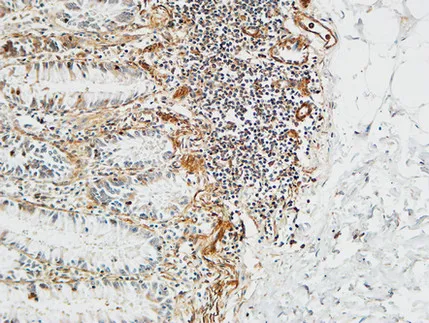

TWEAK Rabbit Polyclonal Antibody

Cat: APRab19441

Size1:50μl Price1:$128

Size2:100μl Price2:$230

Size3:500μl Price3:$980